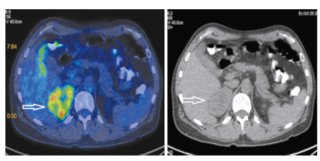

Дополнительно в бифуркационном пространстве под нижней стенкой правого главного бронха определяется узловое образование размером 17×11×24 мм с очаговой фиксацией радиофармпрепарата SUVmax 4.31 (рис. 3).

Рис. 3. Пациент У., 52 года. Аксиальная ПЭТ/КТ- (а) и КТ-проекция (б). У нижней стенки правого главного бронха образование размером 17х11х24 мм (стрелка), SUVmax 7.25.

Fig. 3. A 52-year-old patient U. PET/CT (a) and CT images in axial projection (b). A 17×11×24 mm mass (arrow) at the inferior wall of the right main bronchus, SUVmax 7.25.